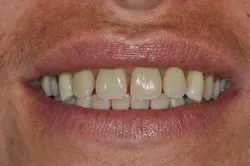

Figs. 8a, b, c, and d: Final results

Figs. 9a, b, and c: Two years’ postop. Note the patient’s commitment to maintaining an optimal oral hygiene